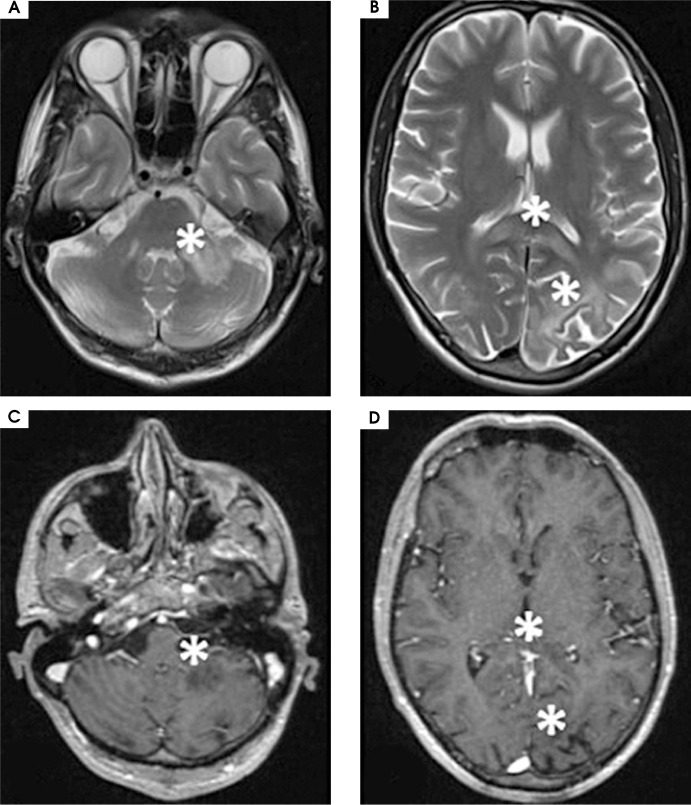

Purpose: Progressive multifocal leukoencephalopathy (PML) is a lethal demyelinating disease of the central nervous system caused by John Cunningham virus (JCV). PML develops due to the reactivation of latent JCV infection in individuals with cellular immunodeficiency. Since the beginning of acquired immunodeficiency syndrome (AIDS) epidemic, human immunodeficiency virus (HIV) infection has remained a leading cause of PML with the condition recognized as an AIDS-defining illness. The clinical manifestations of PML may vary depending on the underlying condition. In AIDS-associated PML, the symptoms include motor weakness, speech or language disturbances, cognitive and behavioral changes and gait abnormalities and incoordination.

Case description: We present the case of a male patient who developed PML as the first clinical manifestation of a newly diagnosed HIV infection.